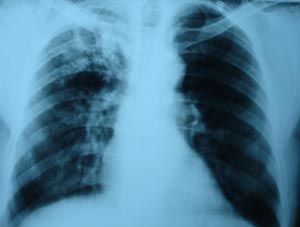

View Pulmonary tuberculosis

Pulmonary tuberculosis